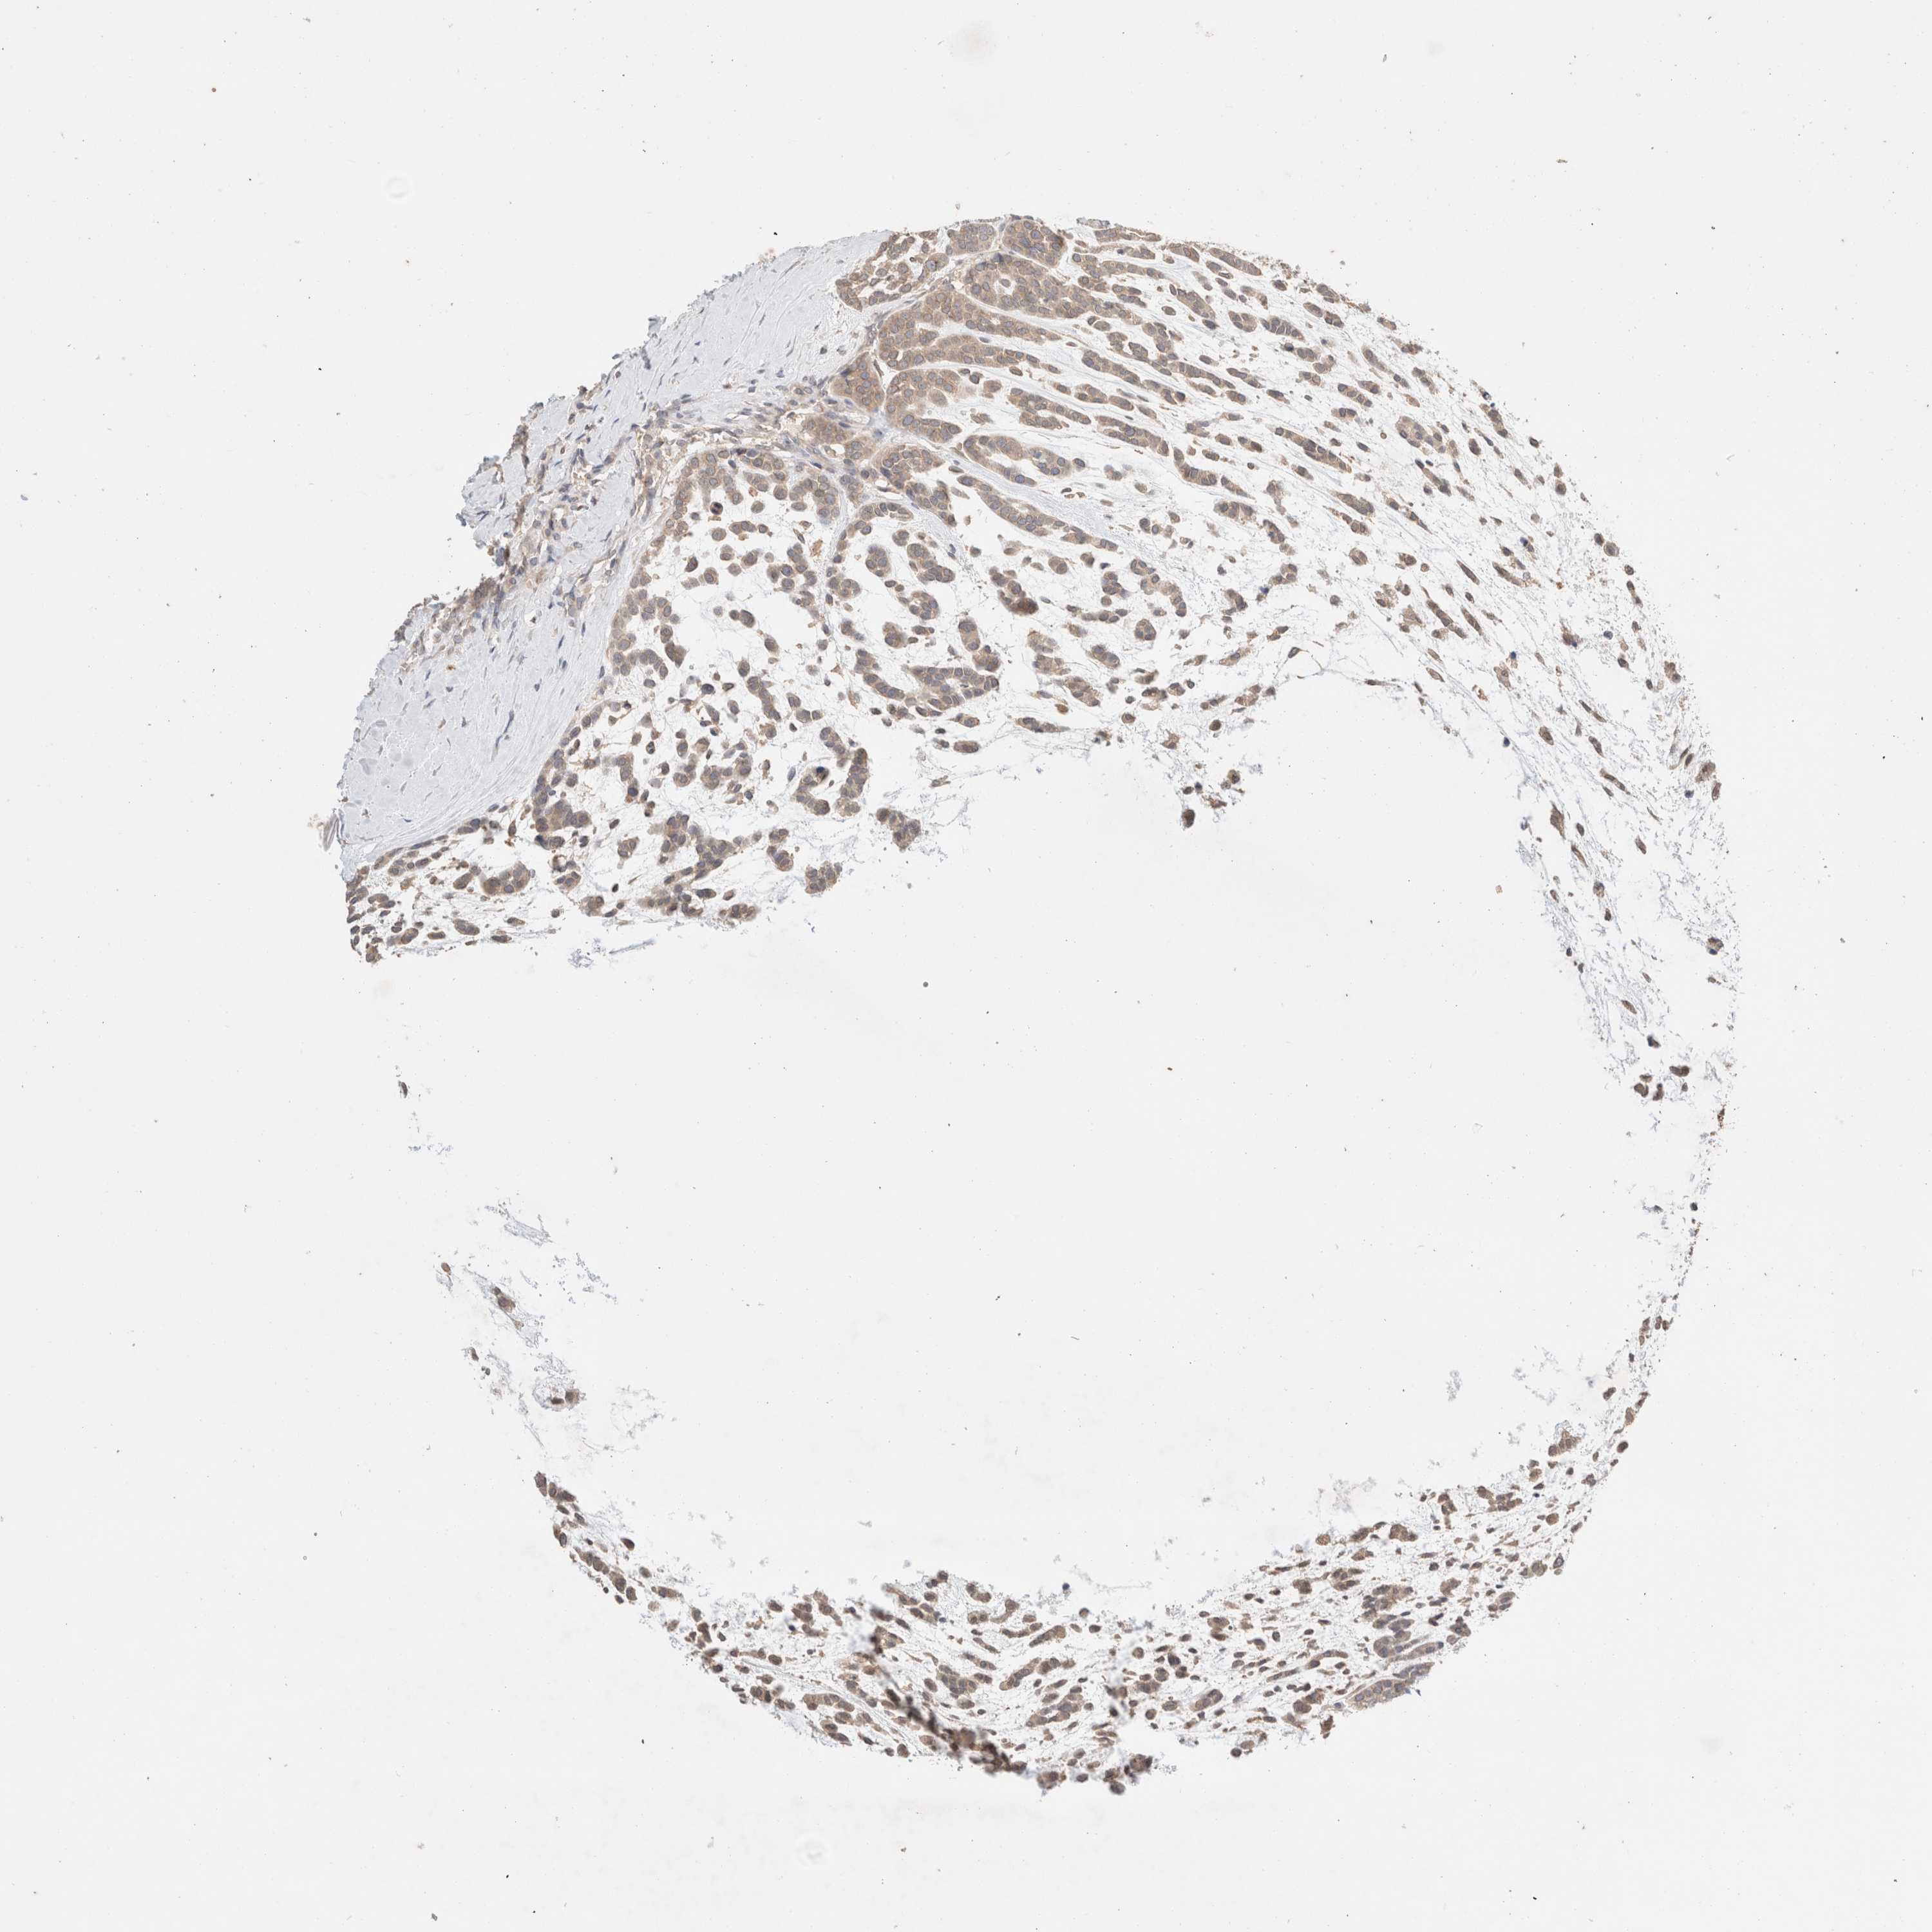

HEAD AND NECK CANCER - Protein expressioni

A mouse-over function shows sample information and annotation data. Click on an image to view it in a full screen mode. Samples can be filtered based on level of antibody staining by selecting one or several of the following categories: high, medium, low and not detected. The assay and annotation is described here.

Antibody stainingi

Antibody staining in the annotated cell types in the current human tissue is reported as not detected, low, medium, or high, based on conventional immunohistochemistry profiling in selected tissues. This score is based on the combination of the staining intensity and fraction of stained cells.

Each image is clickable and will lead to virtual microscopy that enables deeper exploration of all samples and also displays staining intensity scores, fraction scores and subcellular localization as well as patient and tissue information for each sample.

Antibody HPA024204

Staining

High

Medium

Low

Not detected

Intensity

Strong

Moderate

Weak

Negative

Quantity

>75%

75%-25%

<25%

None

Location

Nuclear

Cytoplasmic/membranous

Cytoplasmic/membranous,nuclear

Squamous cell carcinoma, metastatic, NOS